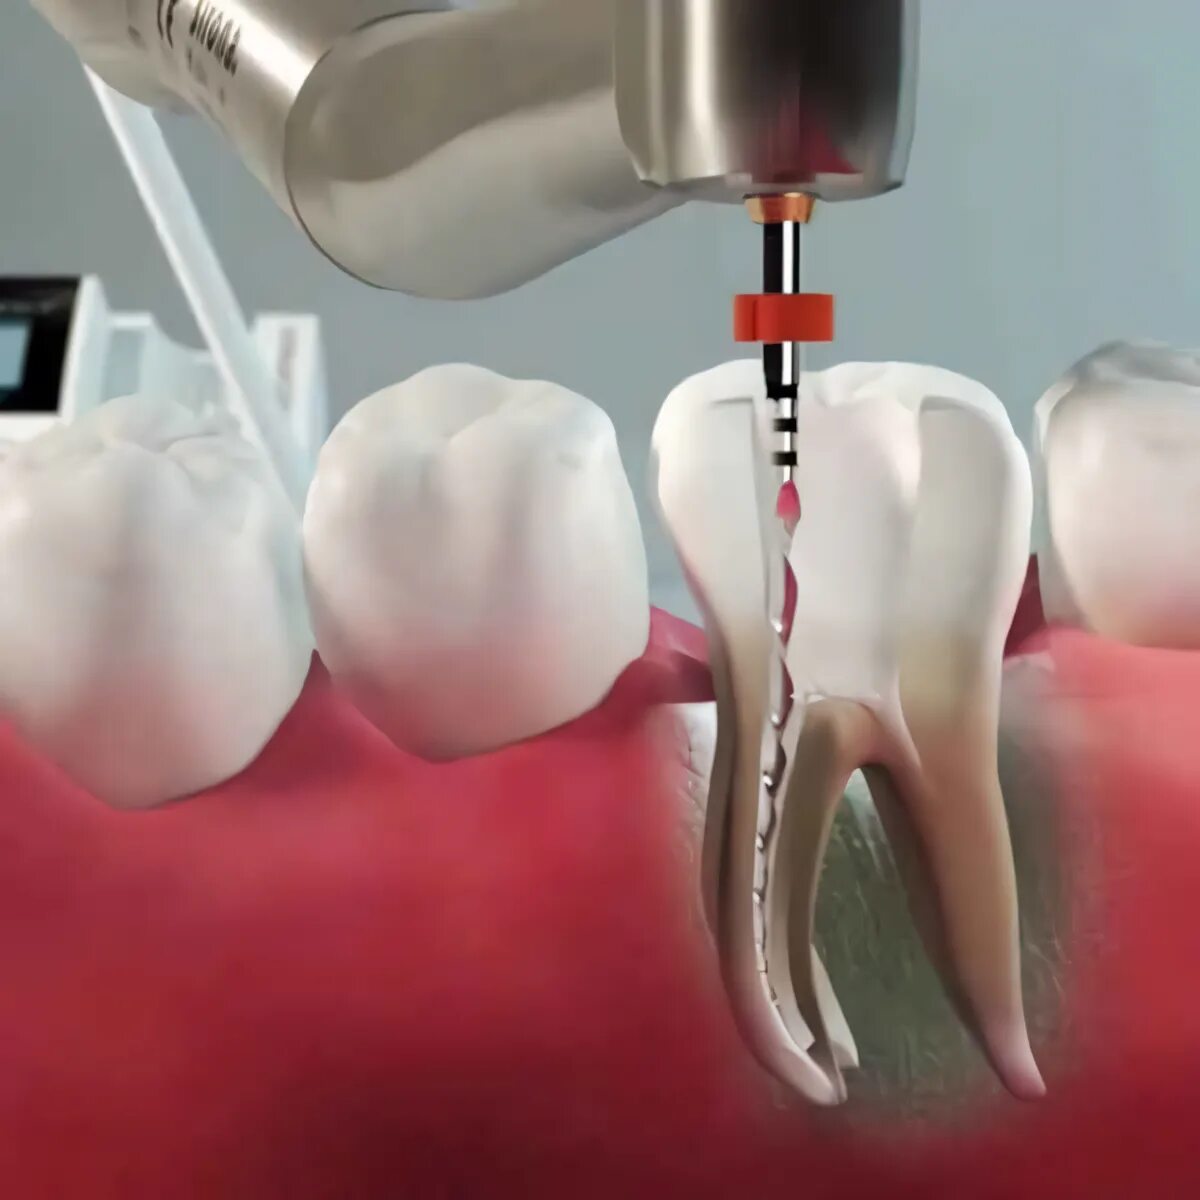

Удаление нервов в зубе и пломбирование